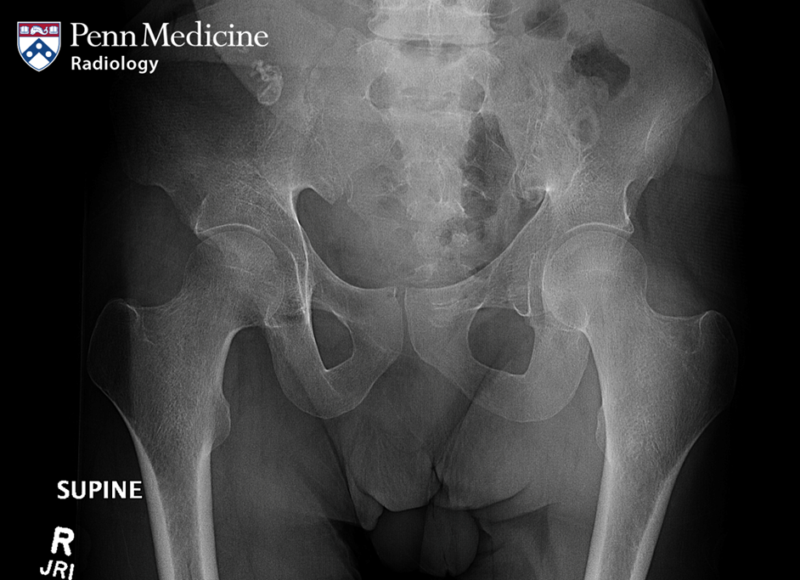

73-year-old man with lower urinary tract infection

A 73-year-old man without significant medical history presented at the urology department of our hospital for a lower urinary tract infection.